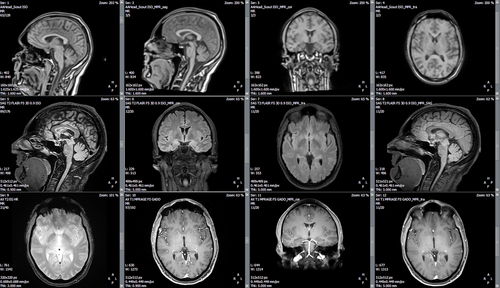

L’arrivée de l’IRM représente certainement un des progrès le

plus important en neurologie et a permis des avancées

thérapeutiques et physiopathologiques majeures. Les cliniciens ont

finalement réussi à se familiariser avec les séquences de bases,

T1, T2, écho de gradient, FLAIR, qui ont été d’un grand apport dans

l’exploration des pathologies tumorales, inflammatoires et, à un

moindre degré,dégénératives. Les séquence de diffusion ou TOF, puis

de perfusion ont permis d’augmenter les indications de

revascularisation dans les accidents vasculaires

cérébraux.